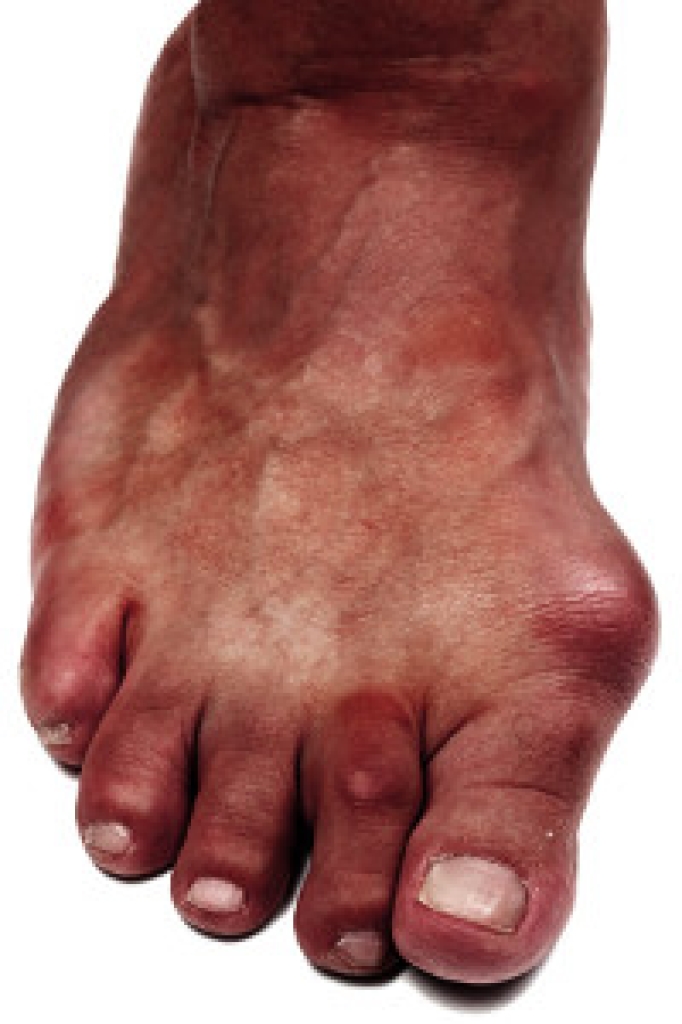

Someone would seek the care of a podiatrist if they have suffered a foot injury or have common foot ailments such as heal spurs, bunions, arch problems, deformities, ingrown toenails, corns, foot and ankle problems, etc.